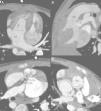

The authors describe the CT findings in a 29-month-old boy referred for cardiac CT angiography to assess complex congenital heart disease. The study was performed on a 128-slice prospectively ECG-gated dual-source Siemens Definition Flash system and showed mesocardia with abdominal/atrial situs inversus (Figure 1), atrioventricular and ventriculoarterial discordance with a subpulmonary ventricular septal defect, and a single coronary artery (Figure 2). Effective radiation dose was 1.0 mSv (dose-length product 25 mGy.cm).

Mesocardia and situs inversus. (A) Topogram; (B) multiplanar reconstruction, coronal view; (C) axial image of the abdomen; (D) three-dimensional volume rendering showing mesocardia, morphological right bronchus in left position, morphological left bronchus in right position, liver on the left, stomach and spleen on the right, and anterior right aorta and posterior left pulmonary artery. Ao: aorta: B: spleen; E: stomach; F: liver; P: pulmonary artery.